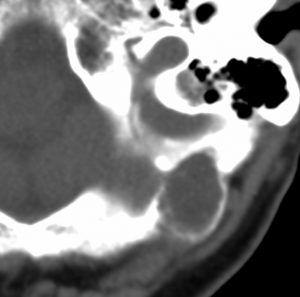

静脈洞交会 confluence に浸潤しているものです。直静脈洞は閉塞しています。右のMRIでは,ガドリニウム増強像が強弱まばらになっています。髄膜腫と診断したいのですが,ちょっと何かが違うというのがSFTです。硬膜や骨や脳に浸潤性格を有します。亜全摘出して術後に54グレイの放射線治療をしました。

5年後に小脳内に再発しました。全摘出したのですが,その後もあちこちに再発を繰り返しています。最初はグレード2でしたが,再発を繰り返すと増大速度が速くなり,再発までの期間が短くなり,多発性再発となってきます。